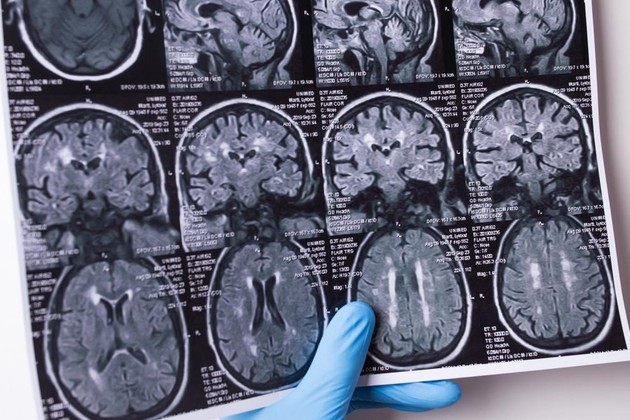

El investigador científico y neurocirujano español Jesús Martín-Fernández encabezará este miércoles el equipo que operará de un tumor cerebral a un paciente que permanecerá consciente durante la intervención para responder preguntas que orienten el procedimiento dentro de su cerebro.

Estará a cargo del neurocirujano español Jesús Martín-Fernández, quien utilizará un método por el que se mantiene despiertos a los pacientes para preservar sus emociones, lenguaje, comportamiento, memoria y otras funciones mentales.

En este método se mantiene despiertos a los pacientes para preservar sus emociones, además del lenguaje, comportamiento, memoria y otras funciones mentales; en estas cirugías, que no tienen antecedentes en Sudamérica, se incluirá un test diseñado por el mismo neurocirujano empleando inteligencia artificial y que permite a los pacientes evaluar sus emociones en vivo y preservar su cognición durante todo el proceso, posibilitando un postoperatorio más corto y llevadero.

"Hay tumores que en muchas casos son tratados con rayos o quimioterapia porque se considera riesgosa una intervención, pero con esta técnica podemos usar un estimulador que genera pequeñas descargas eléctricas en el cerebro y con el paciente despierto podemos ver si eso afecta sus capacidades; para eso desarrollamos unos avatares que expresan emociones que el paciente debe ir identificando y en la medida que el paciente demuestre que el lugar que tocamos no lo afecta podemos seguir avanzando con seguridad para extirpar el tumor", indicó.